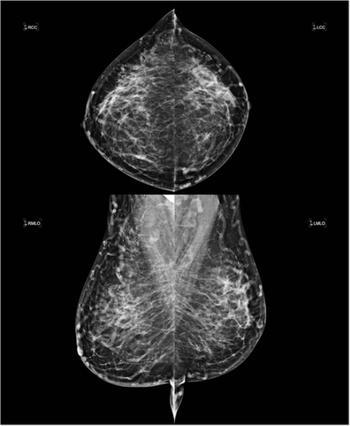

Bilateral Breast Swelling due to Central Venous Occlusion

BySergio Dromi, MD,Erini Makariou, MD

A 47-year-old female with long stand history of hemodialysis and hypertension. No family history of breast cancer. No personal history of diabetes or smoking.